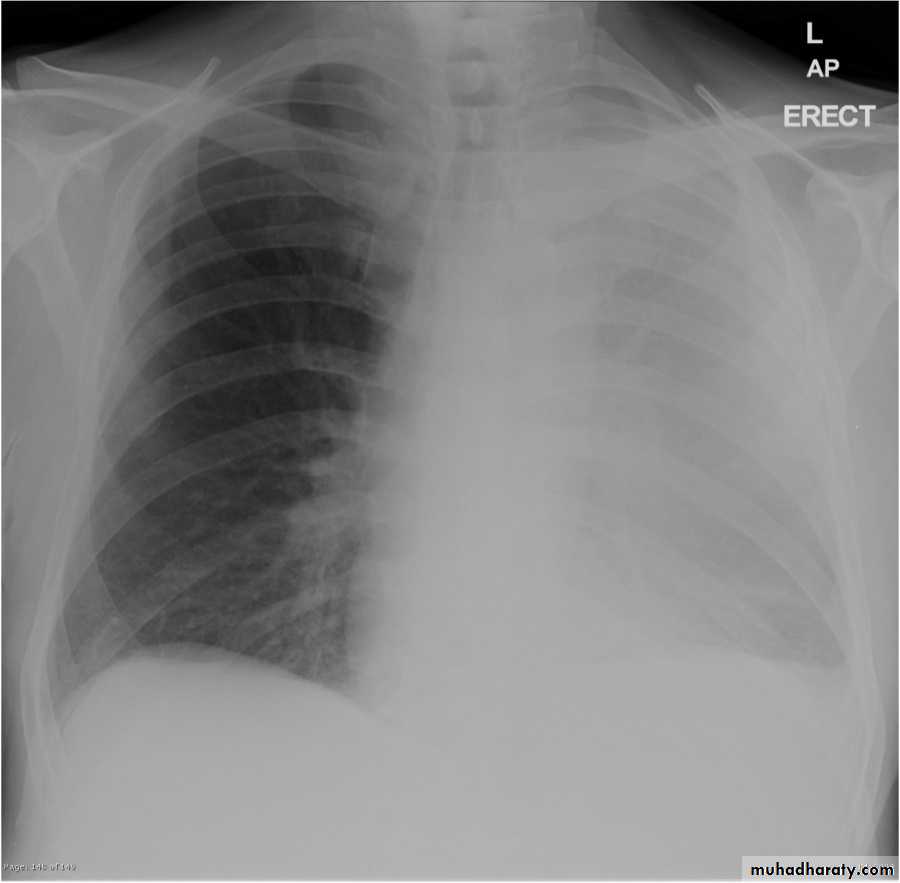

Pleural effusion

48.opasified hemi thorax

50.pleural effusion

51.pleural effusion .